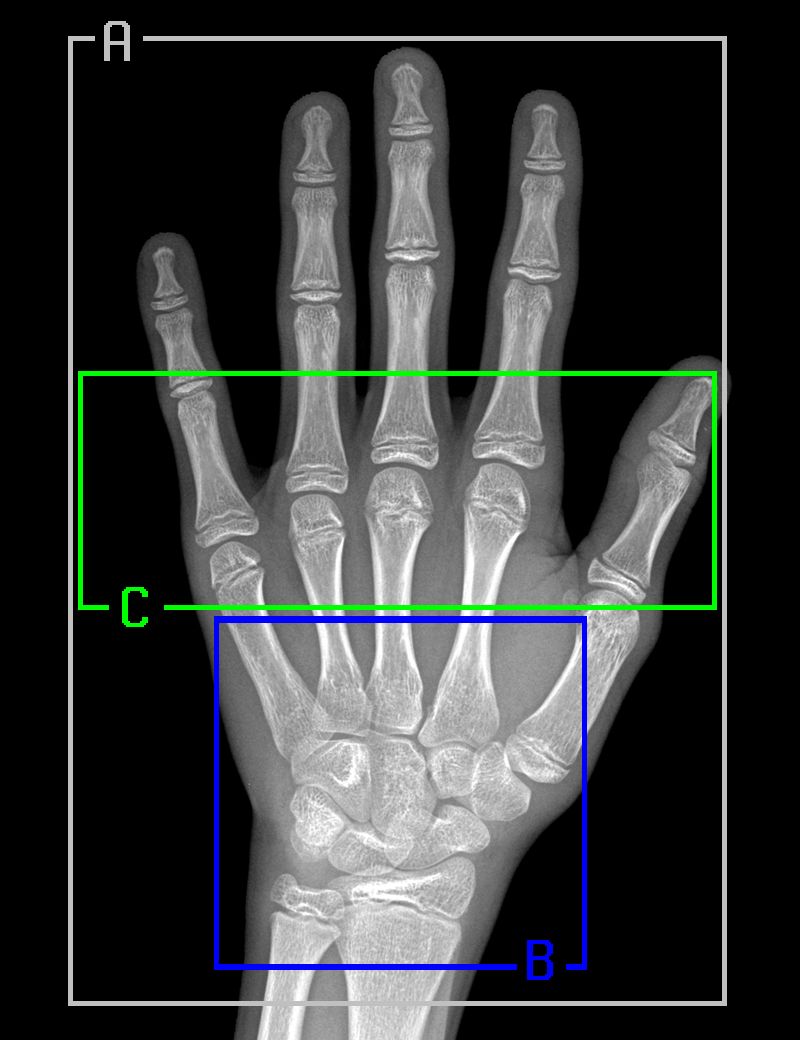

骨龄评估模型 遵循 Gilsanz 和 Ratib 的《Hand Bone Age: a Digital Atlas of Skeletal Maturity》,我们从经过配准的放射影像中选择了三个特定区域,针对每一个区域训练了一个单独的模型: 1. 完整的手骨; 2. 腕骨; 3. 掌骨和近端指骨。 下图是真实放射影像中的上述区域以及相对应的分割样本:

结果证明在输入中添加性别可以将模型准确率平均提高 1.4 个月。最左边这一列表示针对两个性别的回归模型的表现。掌骨和近端指骨区域(区域 C)的 MAE 为 8.42 个月,整个手骨(区域 A)的 MAE 为 8.08 个月。对这三个区域进行线性集成可以将准确率提高到 7.52 个月(表中最后一行)。 性别特定的回归模型(第二列和第三列)将针对男性的模型的 MAE 改善为 6.30 个月,将针对女性的模型的 MAE 改善到 6.49。需要注意的是,就女性而言,掌骨和近端指骨区域的 MAE 为 6.79 个月,甚至比对整个手骨进行预测的结果还准确,后者的 MAE 仅为 7.12 个月。 性别特定的分类模型(第四列和第五列)的结果比回归模型的结果略好,它们的 MAE 分别为 6.16 个月和 6.39 个月(最后一行)。 最后,在第六列,我们将所有性别特定的模型(分类和回归)进行集成。在验证集上,集成模型得到的准确率为 6.10 个月,这也是当前最佳的结果,无论从骨龄评估挑战赛还是从实际应用来看,这都是一个很好的结果。 结论 本文介绍了如何开发可以准确评估骨骼成熟度的自动骨龄评估系统,该系统可以得到与放射科专家相似或更好的结果。我们评估了手骨不同区域,发现可以仅对掌骨和近端指骨进行评估,得到的结果与对整个手骨进行评估的结果相差无几。为了克服放射图像的质量和多样性问题,我们引入了严格的清理和标准化过程,以显著增强模型的鲁棒性和准确率。 我们的模型有极大的潜力部署在临床环境中,帮助临床医生实时判断骨龄。这可以保证在患病儿童出现成长障碍时能进行及时的诊断和治疗。